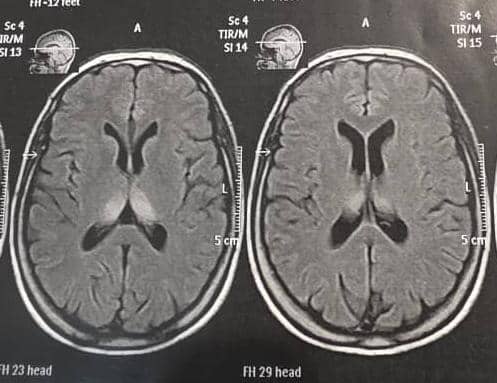

بیمار در بیمارستان سینا بستری و در ام آر آی مغز، ضایعه هیپرسیگنال تالامیک دو طرفه دیده می شود. ( تصویر ۱ )

در بررسی تصویربرداری این بیمار، باید ام آر آی بدون و با تزریق مغز درخواست گردد. در ام آر آی بیمار ضایعات دو طرفه واضح در منطقه دیانسفالون دیده می شود که قویا موید انسفالیت اوتوایمیون و پارانئوپلاستیک است.